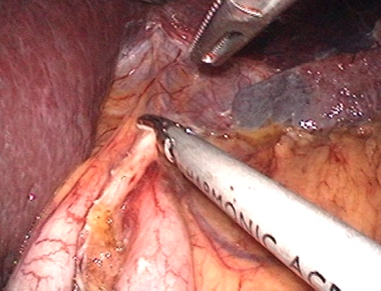

つないだり、切り離しの準備のために食道の周りを十分に露出しておきます。

ホチキスを入れるための穴を食道に開けます。同様の穴を小腸にも開けます。これで小腸と食道をつなぐ準備ができました。

血管の処理が終わるといよいよ胃を全摘出します。そして、持ち上げた小腸と食道をつなぎ合わせます。

つなぎ合わせる手技もお腹の中で行います。

体の深い場所での操作ですが、カメラで拡大されているため周りを確認しながら安全に行うことができます。